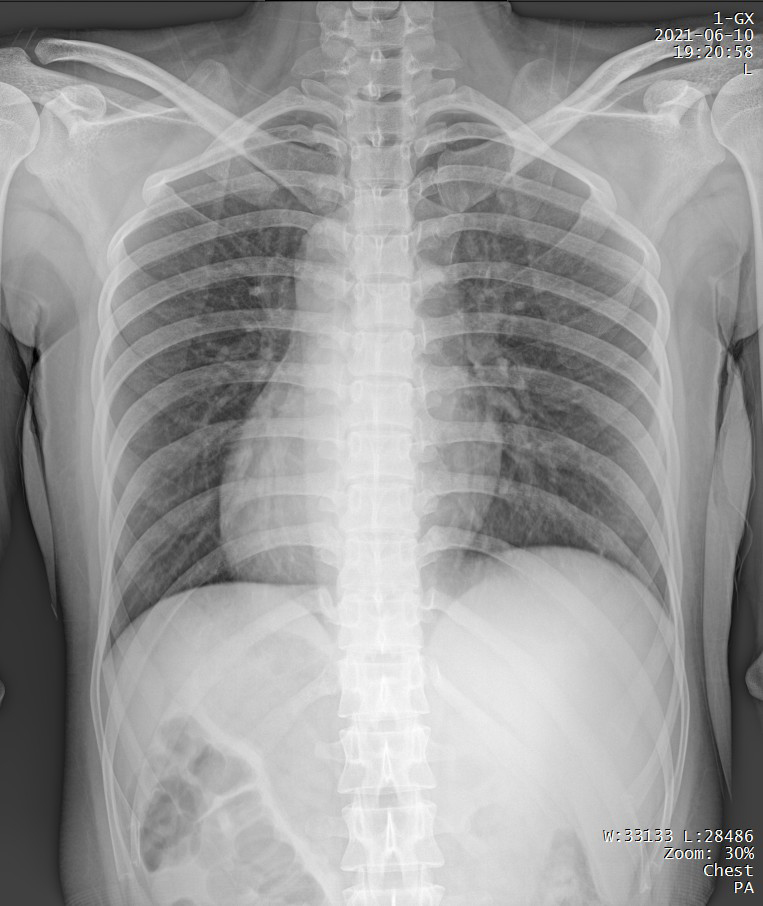

短時曝光 定格心肺運動瞬間的影像

PLX5500能夠在短時曝光內(nèi)輸出足量的X射線,獲取清晰圖像。特別適用于拍攝肺炎、塵肺病、肺結(jié)核等難以憋氣的患者,避免因患者呼吸而產(chǎn)生運動偽影,便于醫(yī)生準確診斷。

支持高千伏攝影 肺部紋理更有層次

PLX5500能夠輸出高能量X射線,與骨骼相重疊的軟組織或骨骼本身的細小結(jié)構(gòu)及含氣的管腔等,均可清晰顯示。

Clinical picture

臨床圖片